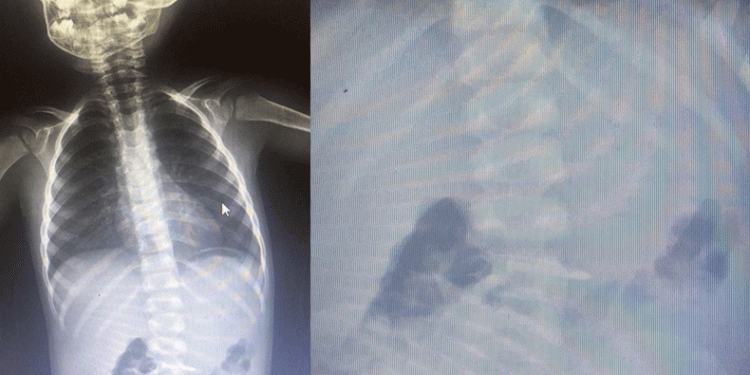

Bursa’da 2 yaşındaki çocuk çivi yuttu

Olay, Mesudiye Mahallesi Sakin Sokak’ta meydana geldi. 2 yaşındaki Asil K., evde oynarken yerde bulduğu çiviyi ağzına atıp yuttu.

Olayı gören ailesi, küçük çocuğu hemen özel araçla İnegöl Devlet Hastanesi’ne götürdü

Yapılan tetkiklerde çivinin midesinde olduğu tespit edilen çocuk, ambulansla Bursa Yüksek İhtisas Eğitim ve Araştırma Hastanesi’ne sevk edildi.

Polis olayla ilgili inceleme başlattı.